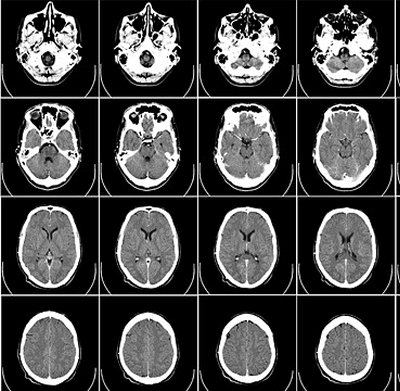

A Imagiologia é a especialidade médica que permite a obtenção de imagens de diversos órgãos e sistemas, utilizando diferentes metodologias, como as radiações, ultrassons ou ondas de radiofrequência, para fins de diagnóstico e terapêutica.

A Unidade de Imagiologia da Clinica São Domingos está equipada com as seguintes valências da Imagiologia Clínica tais como a Radiologia Convencional Digital, Ecografia, Eco-Doppler, Mamografia Digital, Ortopantomografia e Telerradiografia.